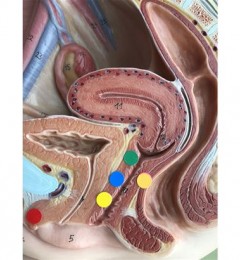

不宁腿症是一种神经系统的疾病,通常是小腿以下感到不适感。此疾病的表现症状相当多样化,每位病人的感受不尽相同,有的人形容皮肤发痒,像是有虫子在爬、蚂蚁在咬或是有灼热感等,但共通点是夜间时症状加剧,白天反而无异状,这种疾病严重时会导致睡眠困难,隔天精神疲倦,长期累积下来会影响到情绪、社交及工作表现。

不宁腿症的治疗?

目前,患不宁腿症的病人年龄从25~60岁不等,病因可能包括贫血、怀孕、药物副作用、熬夜或生活压力,由于一般民众对这种疾病较不熟悉,容易被忽视,但其对生活的影响不容小觑。幸运的是,不宁腿症并非绝症,透过及时诊断和有效的药物治疗、调整生活方式,大部分病人的症状都能改善。医生建议,如有难以入睡或睡不好的情况,应寻求神经内科或睡眠医学专科求助,及时就医,才能尽早改善生活质量。